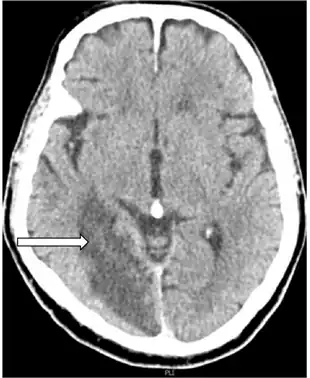

| Anton syndrome because of Bilateral Ischemic Occipital Lobe Strokes-image indicates nonhemorrhagic cerebral infarction arrow | |